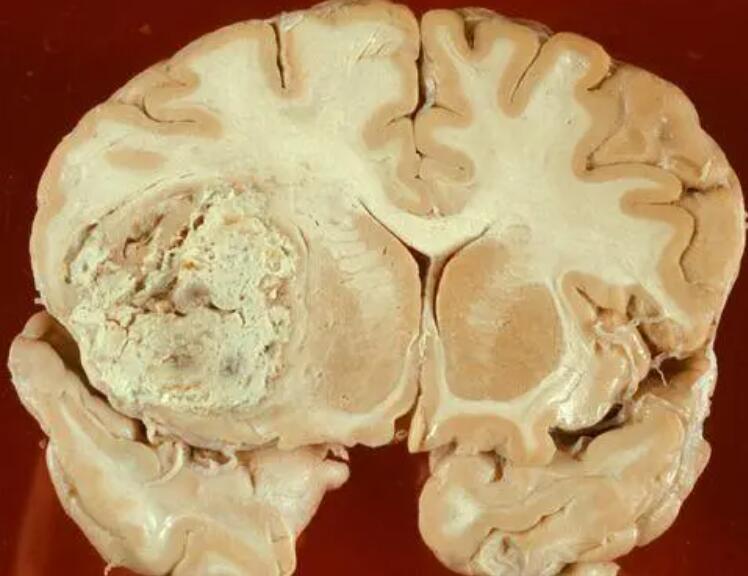

背景:GBM治疗的挑战与需求

胶质母细胞瘤是一种高度侵袭性的脑肿瘤,传统治疗方法效果有限,因此寻找更有效的治疗手段一直是医学界迫切的需求。olaptesed pegol作为CXCL12抑制剂,与VEGF抑制剂贝伐珠单抗和放疗的联合治疗显示出了显著的潜在生存优势。